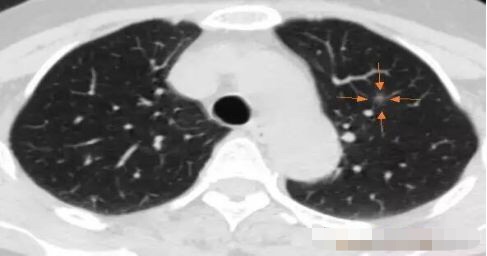

病例4

2013年发现, 每年随访,随访至2016年,病灶逐步增大,2013年5毫米大小,2016年11毫米,3年生长6毫米,平均每年2毫米